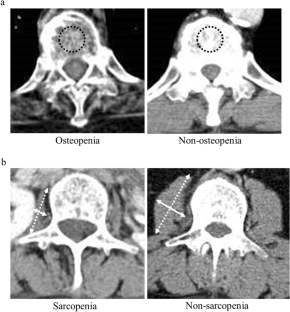

Fig. 1